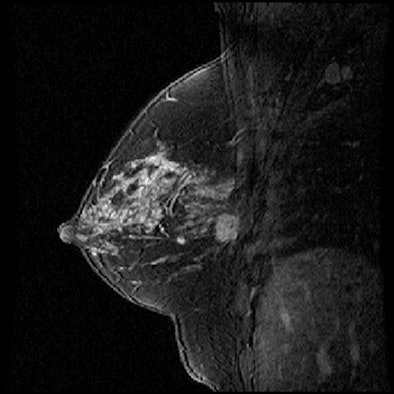

| Contrast-enhanced 1.5-tesla MR images show a patient at low risk of breast cancer recurrence (above) and a patient at high risk (below). |

Daye and colleagues analyzed seven characteristics of the tumors as seen on MRI: size, multifocality, shape, margin morphology, enhancement amount, enhancement kinetics, and associated nonmass enhancement.

Daye and colleagues found that of the MRI-based tumor features, multifocality and lesion size were most significant in predicting the recurrence risk categories on the Oncotype DX assays (p < 0.05). Using three of the MRI tumor features, including multifocality and lesion size, produced the most significant agreement in predicting the Oncotype DX recurrence risk categories (kappa = 0.41, p = 0.01).

Based on the results, the researchers concluded that breast MRI tumor features could help predict breast cancer recurrence, with multifocal and larger lesions appearing to increase risk. When combined in a linear discriminant analysis model, the tumor features can predict the risk category of the Oncotype DX assay, according to the group.